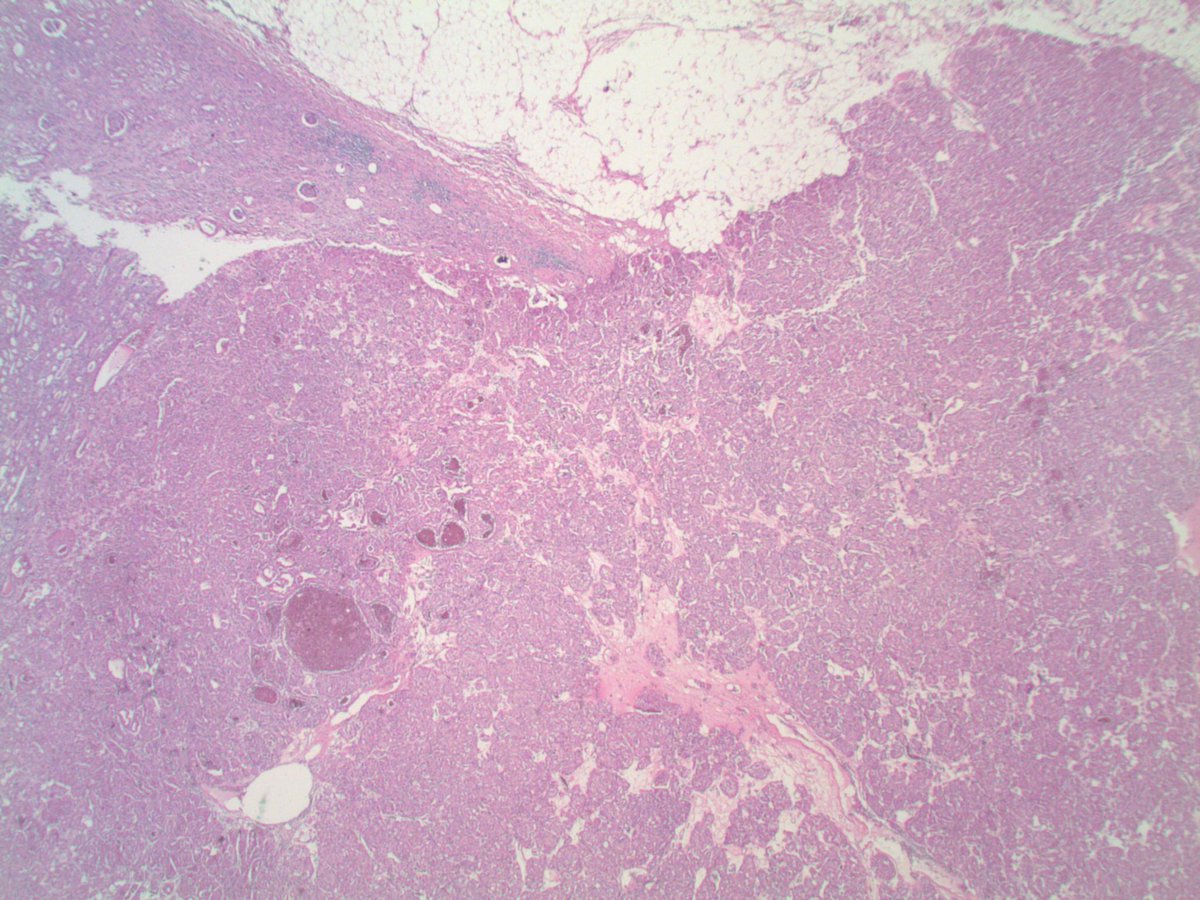

Collision of clear cell renal cell carcinoma and papillary renal cell carcinoma! This #prcc is trying to invade #ccrcc! #PathTwitter #gupath

0

3

9